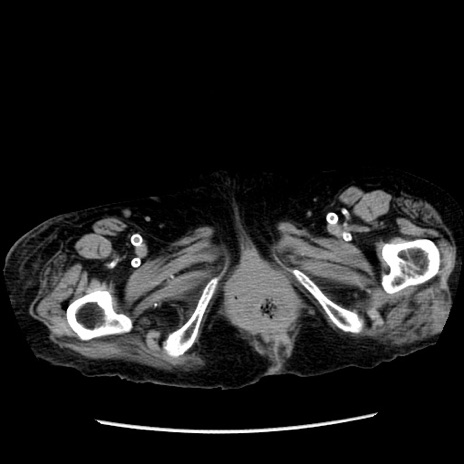

症例14(横断像)

【症例】 90歳代女性

【主訴】 腹痛・嘔吐

【現病歴】今朝から左側腹部痛を認めた。 経過観察していたが、嘔吐を認めたため来院。

【既往歴】 子宮癌術後

【身体所見】 意識清明、BP 127/54mmHg、P 98bpm Sp02 95%(RA)、BT 35.8°C、腹部平坦・軟腸ぜん動音聴取良好、右下腹部圧痛(+) 反跳痛なし

【データ】WBC 9800、CRP 0.46